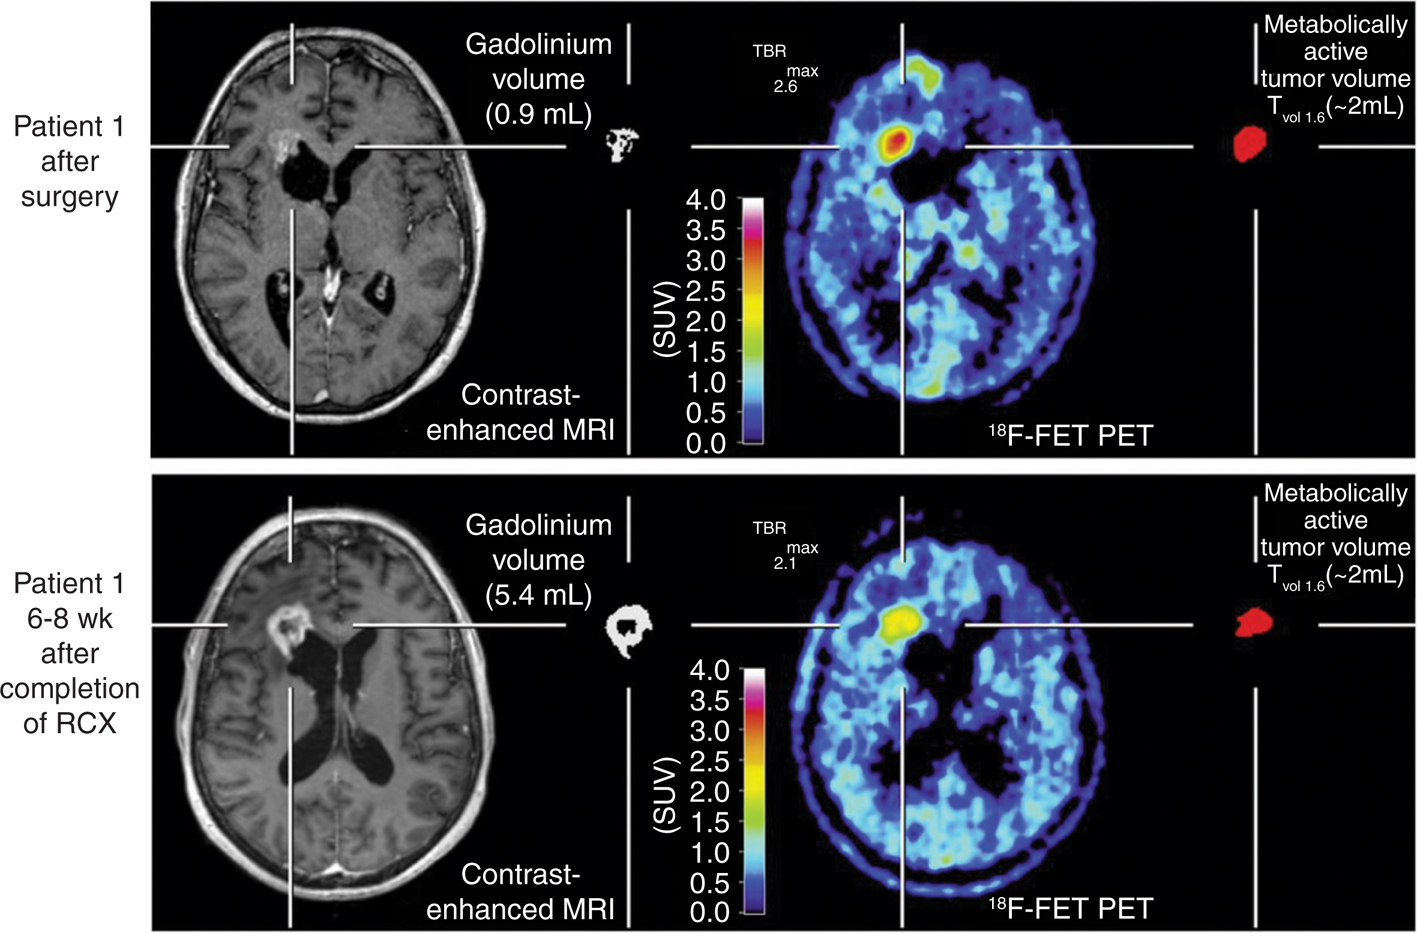

With regard to the differential diagnosis between tumor recurrence and radionecrosis, 11C-MET provides a better sensitivity and clearer delineation of the suspected recurrence (83). In a comparative study, 11C-MET was found to be superior to 18F-FDG for diagnostic accuracy in distinguishing glioma recurrence from radiation necrosis (95). Similarly, in a prospective comparison with 18F-FDG PET, 18F-FDOPA PET had a diagnostic accuracy of 100% for the diagnosis of glioblastoma recurrence versus 92.8% with 18F-FDG PET (96). In addition, in a study of 110 glioblastoma patients, 18F-FDOPA PET detected recurrence with high accuracy while lesion-to-normal-tissue ratios were predictive of progression-free survival (97). Finally, 18F-FDOPA PET is also able to distinguish tumor recurrence from treatment-related changes (24), an example of which is depicted in Figure 4. In a similar manner, static and dynamic 18F-FET PET parameters can differentiate progressive or recurrent glioma from treatment-related nonneoplastic changes with a higher accuracy than conventional MRI, especially with regard to glioblastoma recurrence (98, 99).

Fig 4

Figure 4 Left temporal glioblastoma recurrence in a 66-year-old man after surgery and adjuvant radiochemotherapy. The axial slice of Fluid-Attenuated Inversion Recovery (FLAIR)-weighted MRI (left side) shows a hypersignal at the posterior area of the exeresis cavity (white arrow), making the distinction between tumor recurrence and post-therapeutic effects somewhat challenging. The axial slice of 18F-FDOPA PET shows an intense uptake in the same area (white arrow), which is strongly in favor of tumor recurrence.